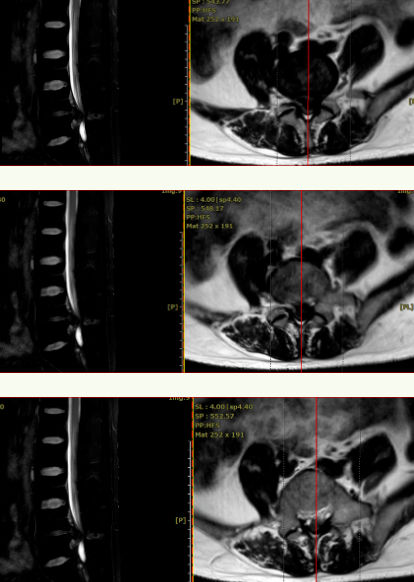

术前CT见:腰4/5椎间盘巨大凸出向后下方,左侧旁中央及侧隐窝狭窄明显,伴腰4、5椎体后缘钙化。

腰椎MRI见:腰4/5椎间盘变性,椎间盘巨大突出,硬膜囊受压明显,左侧椎间孔明显狭窄,左侧神经根受压明显。